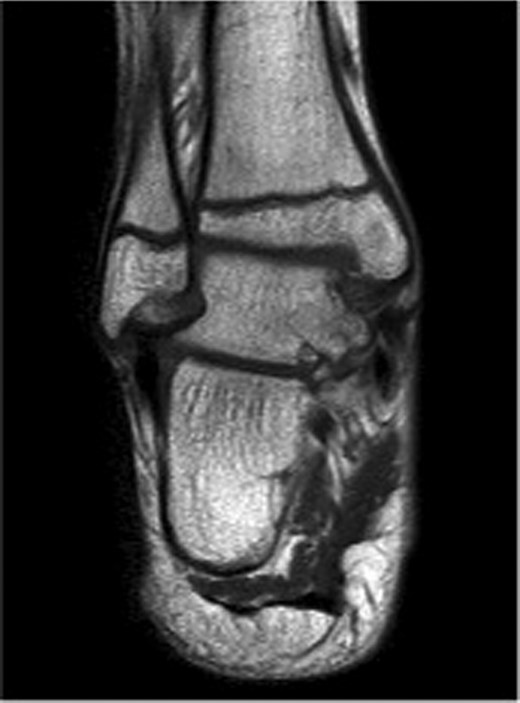

The patient subsequently underwent a manipulation under anaesthesia and POP application of his left distal tibia and right ankle to correct the talar displacement. Despite this, post-operative radiographs of the right ankle showed persistent widened medial tibio-talar joint, and the patient developed considerable right ankle pain and soft tissue swelling which did not correspond with the initial radiograph findings. Magnetic resonance imaging (MRI) of the right ankle joint was performed which revealed extensive marrow oedema through the medial malleolus epiphysis and the medial body of the talus. There was evidence of disruption of the medial cortex of the talus which explained the widened medial tibio-talar joint (Fig. 2). No disruptions of the epiphyseal plates or ligamentous structures were identified. The injury around the tibio-talar joint was identified as an undisplaced fracture through the postero-medial talus with a corresponding ‘kissing’-type lesion of the inner surface of the medial malleolus with gross soft tissue oedema. In view of the overlooked skeletal injury, a further computer tomography (CT) scan of the ankle joint was performed which confirmed a fragmented undisplaced fracture of the postero-medial aspect of the talus, with the anterior subtalar joint remaining intact and an undisplaced fracture through the medial malleolus (Fig. 3).

Right ankle CT axial view demonstrates undisplaced compression fracture of the medial body of the talus.